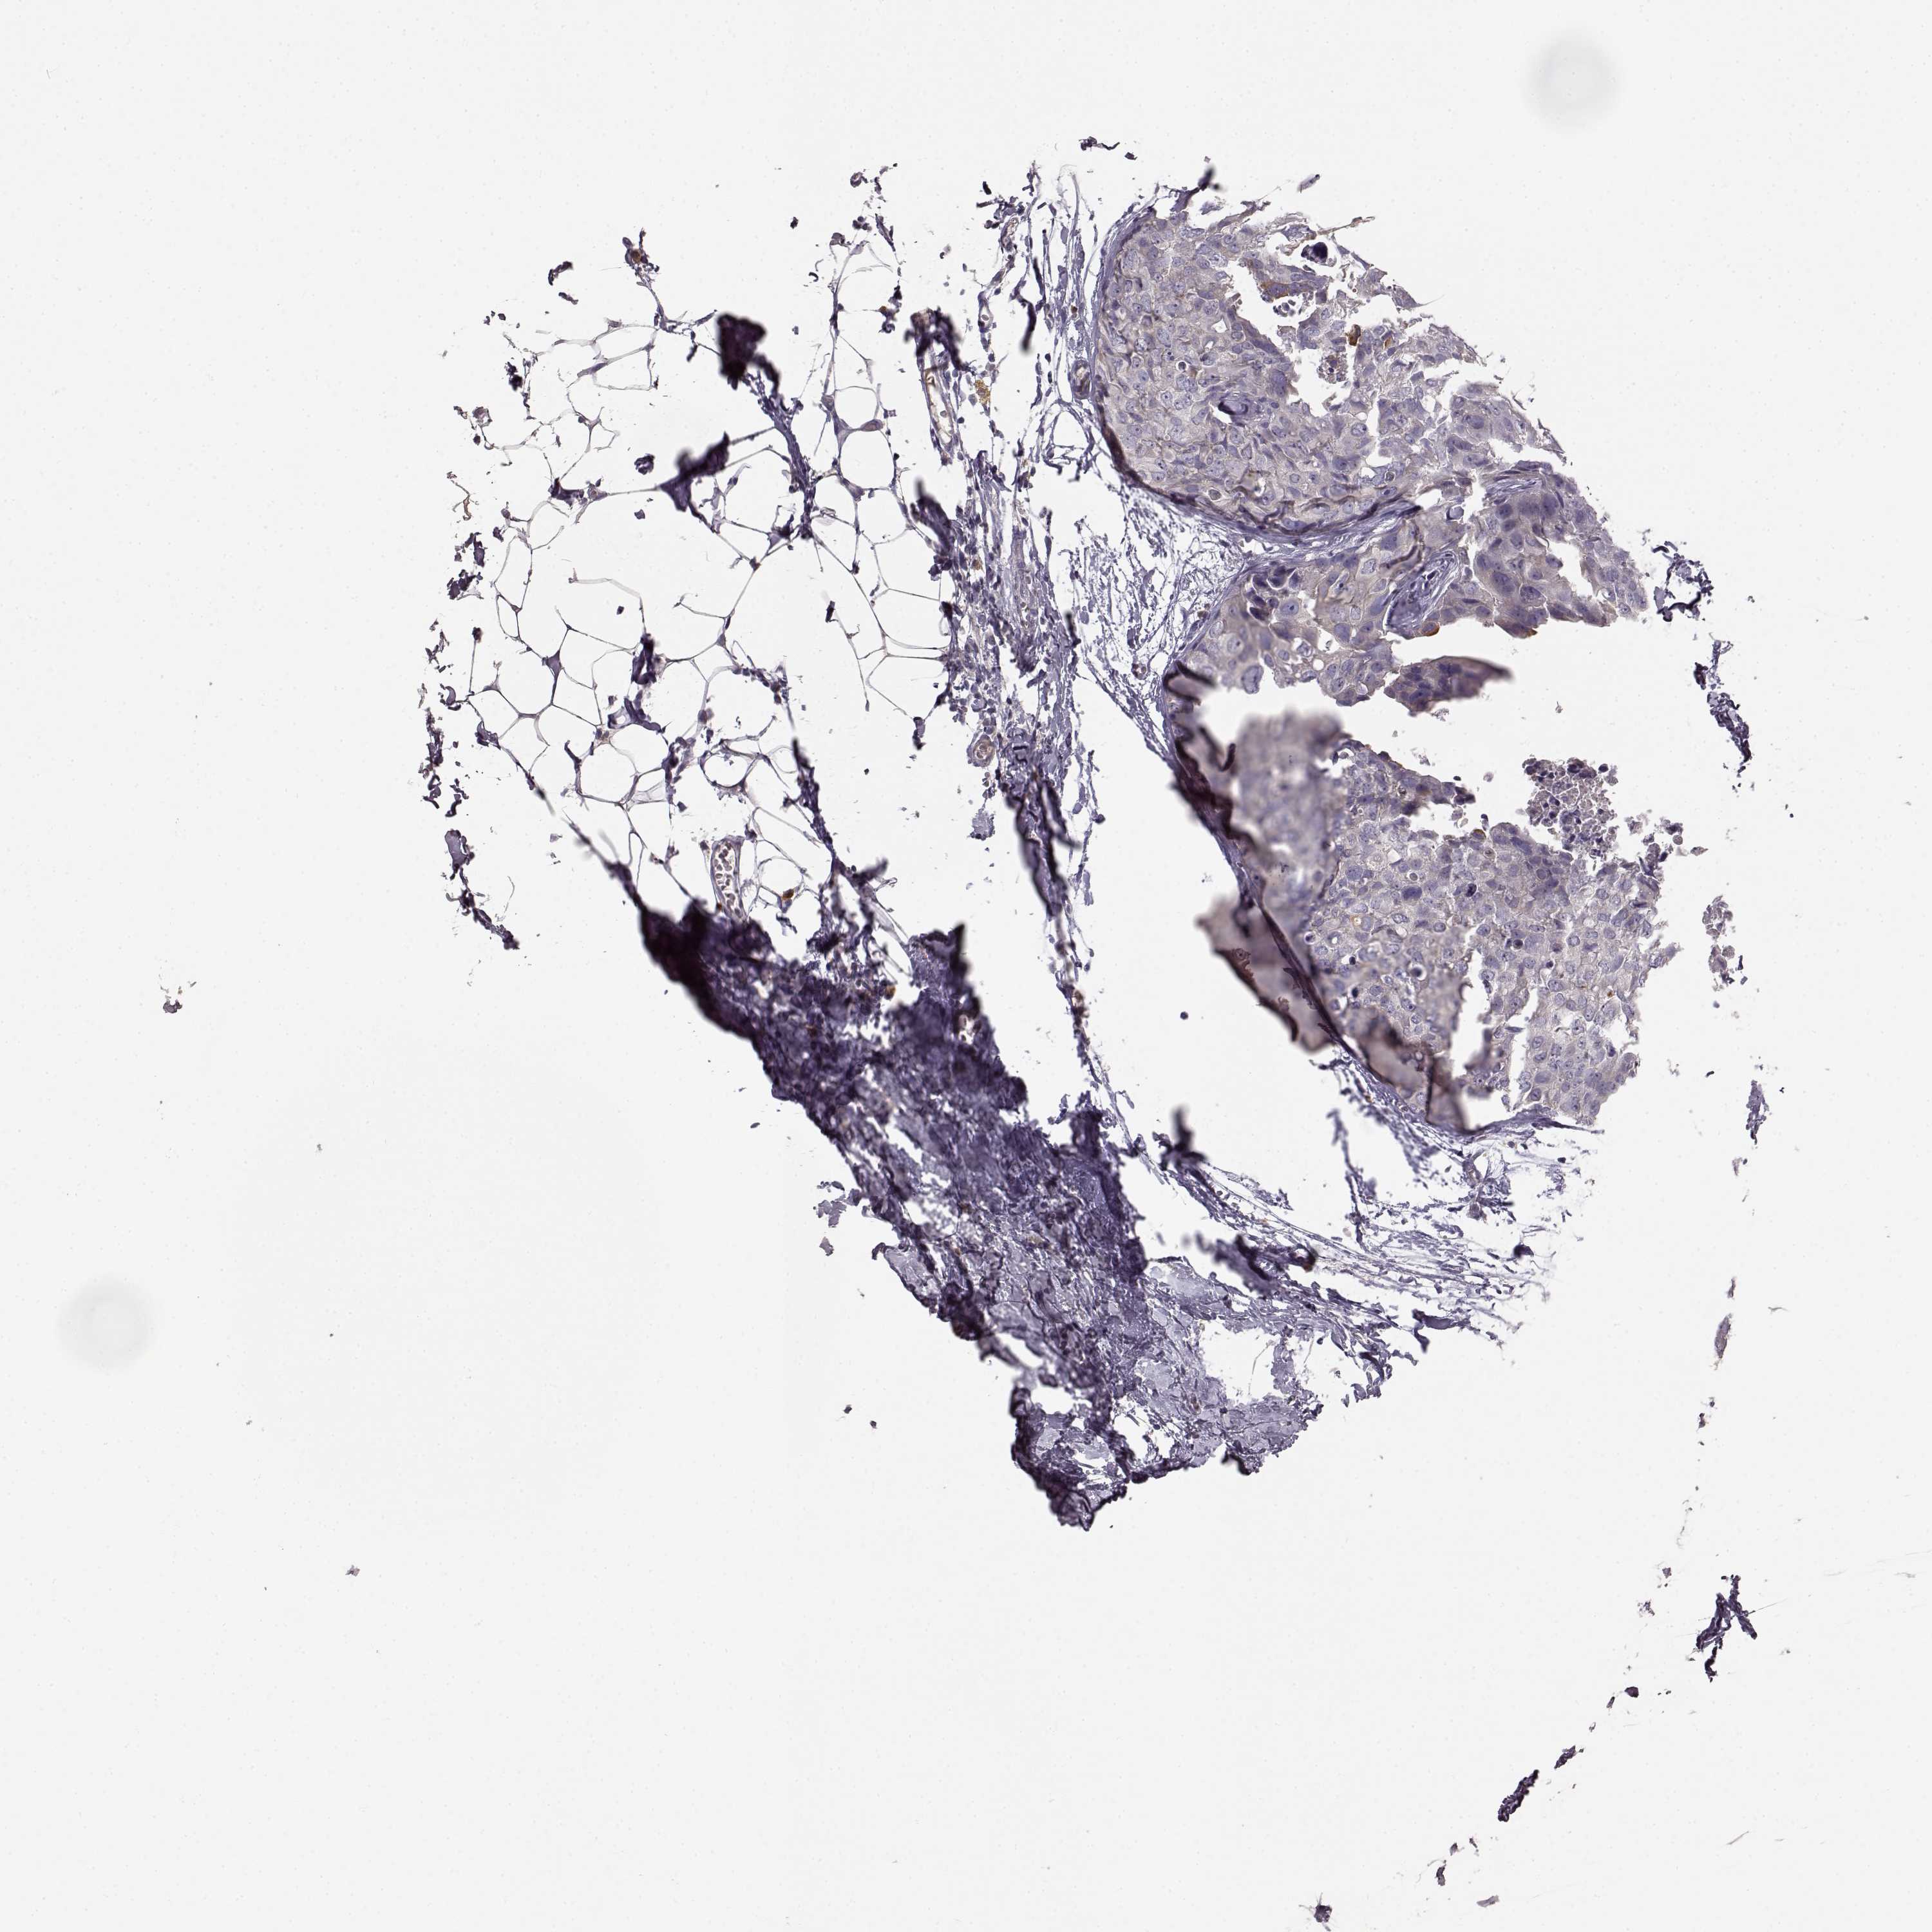

CANCER BREAST CANCER Show tissue menu

BRCA TCGA BRCA VALIDATION PROTEIN EXPRESSION